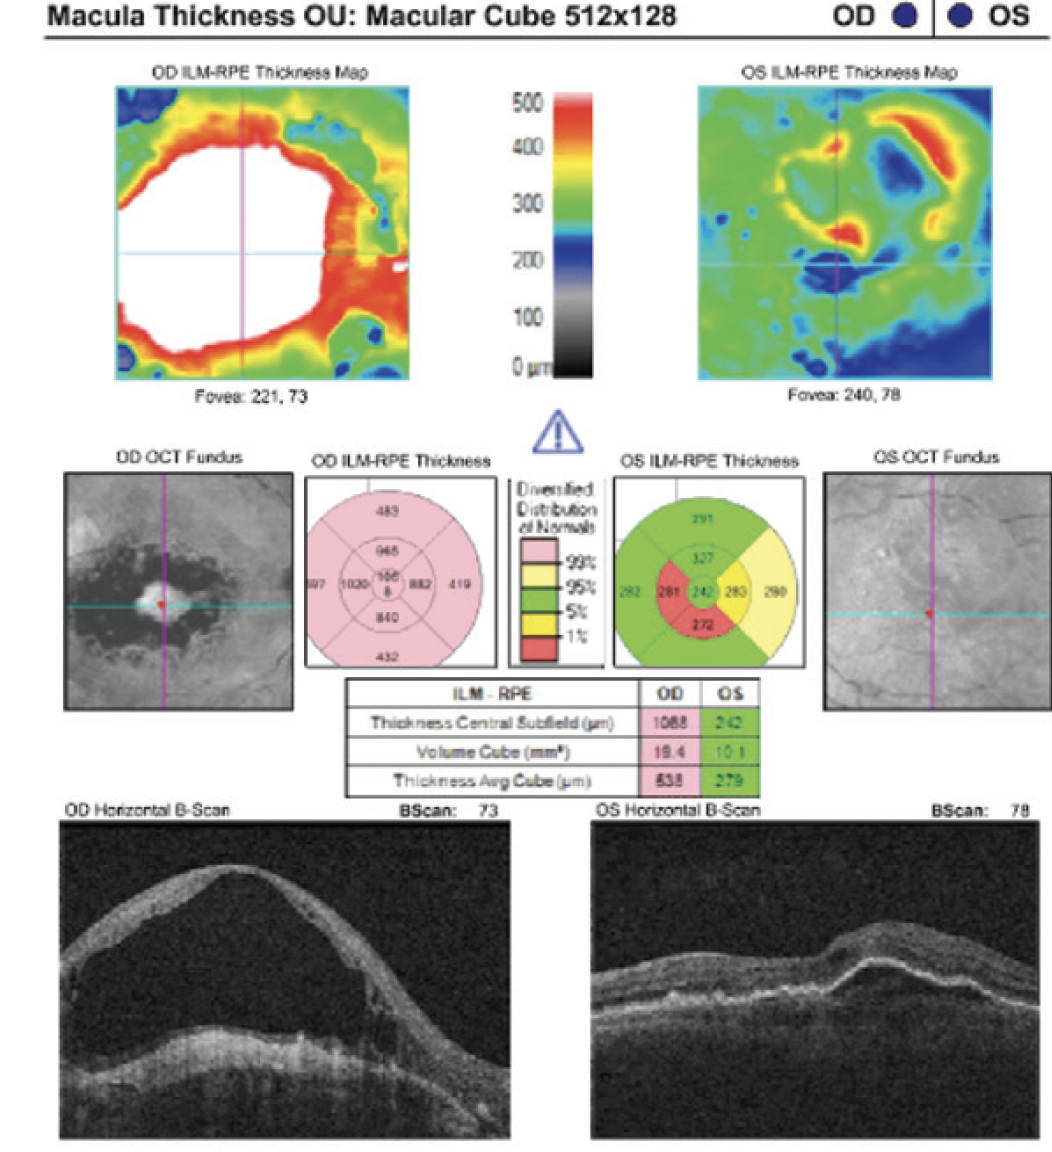

Caroline R. Baumal, MD: Around Christmas 2019, she missed two anti-VEGF injections. After that she came back with recurrent subretinal and intraretinal fluid (Figure 4).

Figure 4. The patient unfortunately missed 2 injections, leading to return of intraretinal and subretinal fluid.